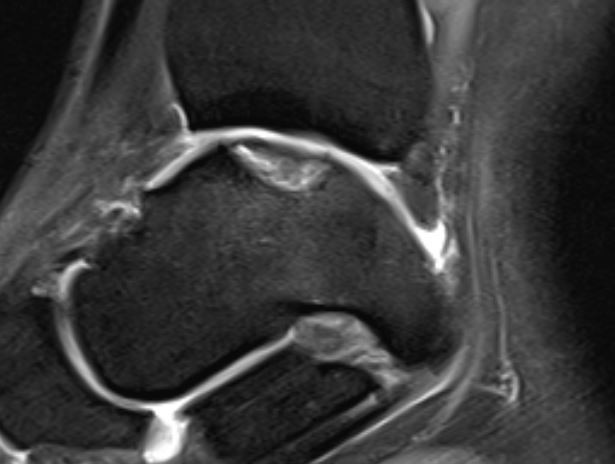

Home Schwerpunkte Krankheitsbilder Osteochondrale Läsion des Talus (OCL) – Ursachen, Symptome, MRT/DVT-Diagnostik & moderne Therapie Osteochondrale Läsion Talus

Osteochondrale Läsion Talus